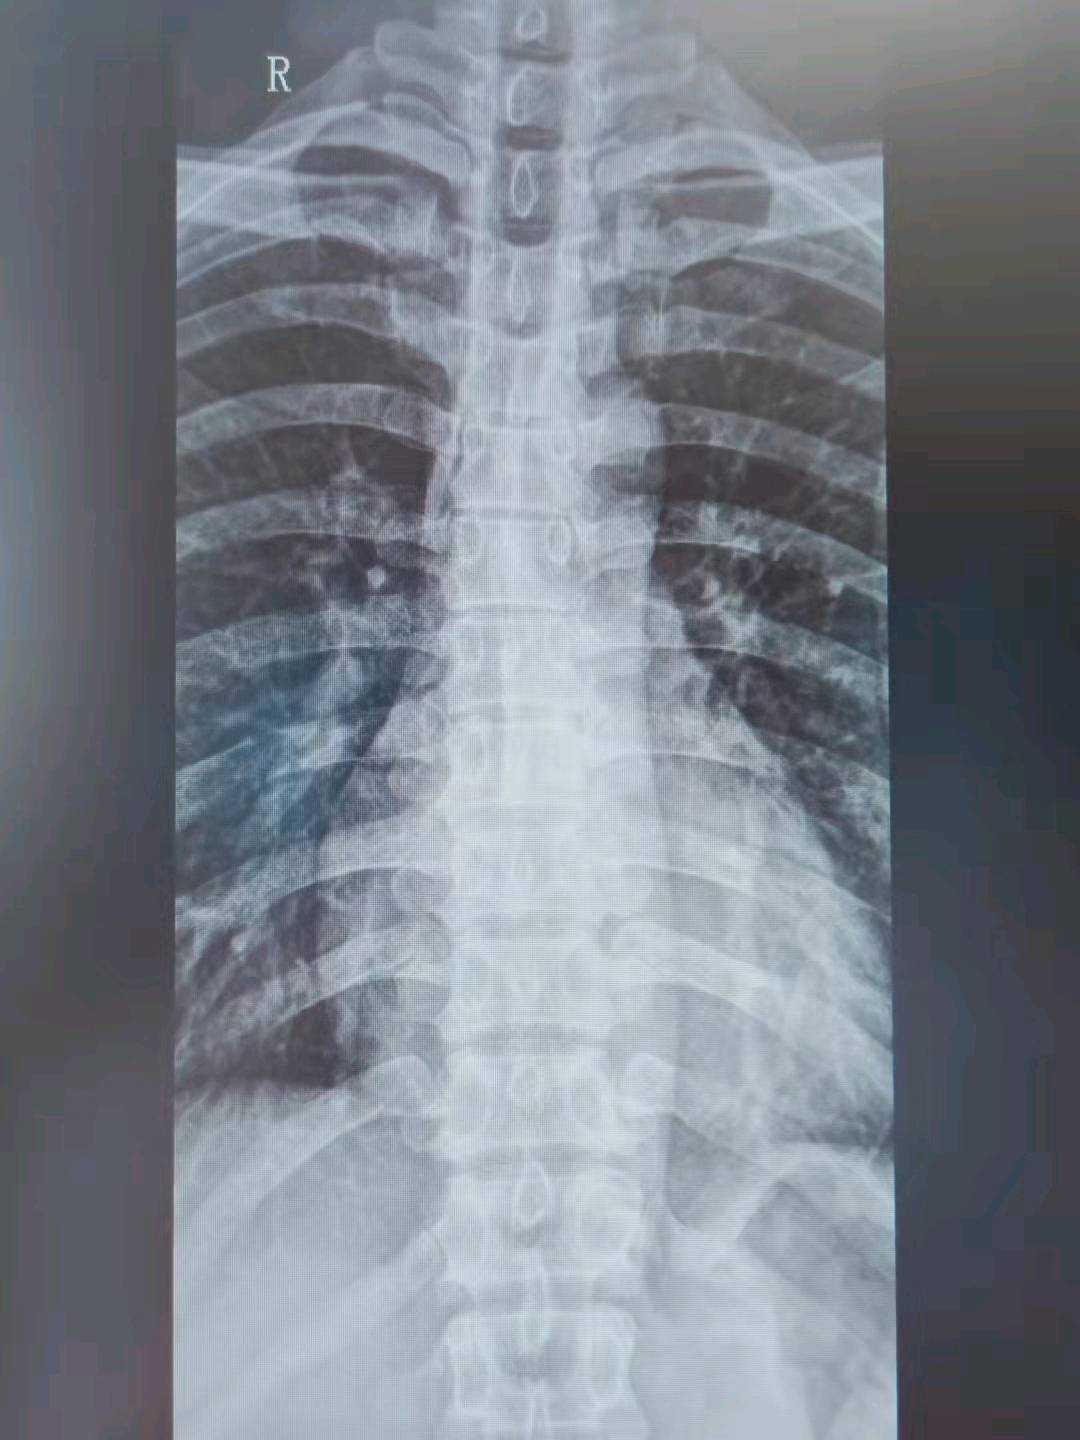

影像:胸椎正侧位提示:胸椎轻微向左侧弯,余未见明显异常。

T5-7棘突疼痛,颈椎前屈加重,T5-7棘突压痛(+),诊断为棘上韧带损伤。T5-7棘突两侧疼痛,颈椎后伸加重,T5-7棘突两侧压痛(+),X线见胸椎侧弯,诊断为胸椎小关节紊乱。项部僵硬,双侧肩胛提肌紧张,压痛(+),双侧后斜角肌紧张,压痛(+),双侧C2-C7横突后结节压痛(+),颈椎前屈、后伸运动模式异常,结合患者多年颈椎病史,诊断为颈椎病。